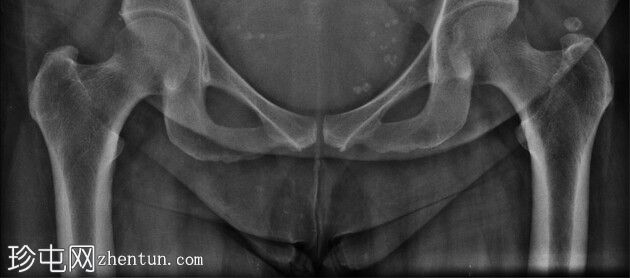

X线片

1.jpeg

正位片

盆腔两侧坐骨棘上方、下方及水平可见多发小片状高密度影。尿道及肾区未见明显高密度影。